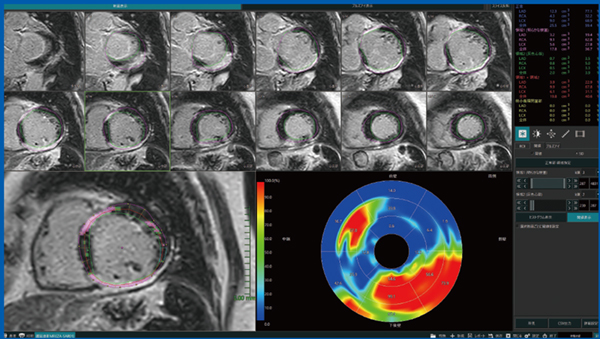

心筋梗塞においては,重症度の進展に伴い虚血の範囲が前壁中隔の内膜側から外膜側へと徐々に広がるwave front現象が知られている。LGE MRIは,梗塞巣を高信号に描出するため心筋バイアビリティ診断に有用で,梗塞巣の壁内深達度50%以上では血行再建による心機能改善の効果が乏しいと判断できる。そのため,ワークステーションを用いて心筋バイアビリティ診断を正確に行うことが,患者の管理や予後改善に重要である。特に,左室心筋全体における梗塞心筋の割合(%LGE)は,左室駆出率(LVEF)や左室容積(LVEDV)よりも有用な予後規定因子であることが報告されており,ワークステーションにて%LGEを正確に測定することが求められる。Abierto Visionは,左室および右室の機能解析はもとより,LGE定量解析(%LGEの算出)にも対応している。また,心機能解析において重要なトレーシング機能の精度も良好である。図1は,Abierto Visionによる陳旧性心筋梗塞症例のLGE定量解析画面である。心筋造影効果がカラーでわかりやすく表示され,%LGEも算出されている。

図1 LGE定量解析:陳旧性心筋梗塞